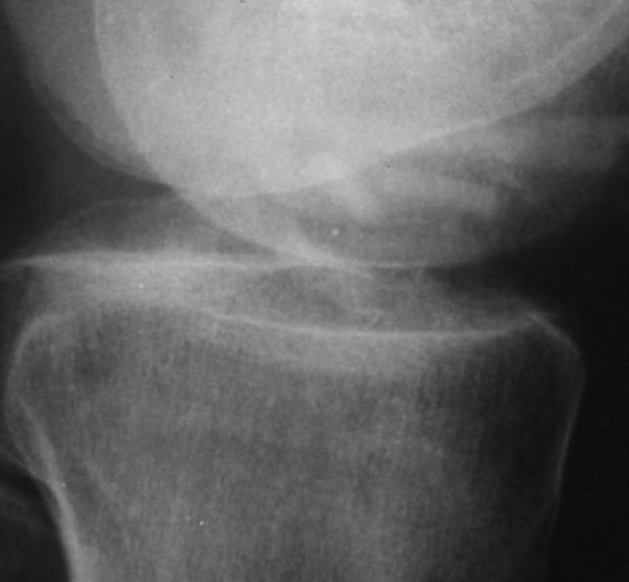

Situs intraoperativ

6 Monate postoperativ Knochenschrauben-Transplantate sind gut sichtbar. Keine Osteolysen erkennbar.